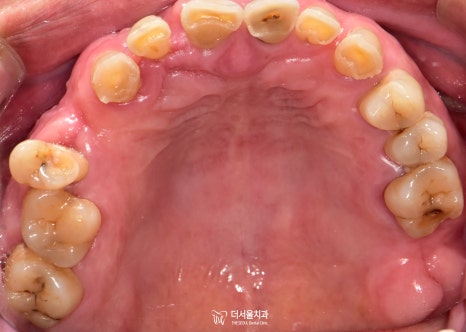

초진 구강 사진을 보면

곳곳에 이가 빠져서 빈 곳이 있고

남아있는 이들이 깨지고

벌어져있습니다.

그런데 문정역치과 환자분의 경우,

면종류를 끊어먹는 정도의 기능을 하는

앞니가 어금니의 역할을 대신하게 되면서

그 힘을 견디지 못하고

이가 부러져버리고 벌어지는

문제가 생겨나게 된 것이죠.